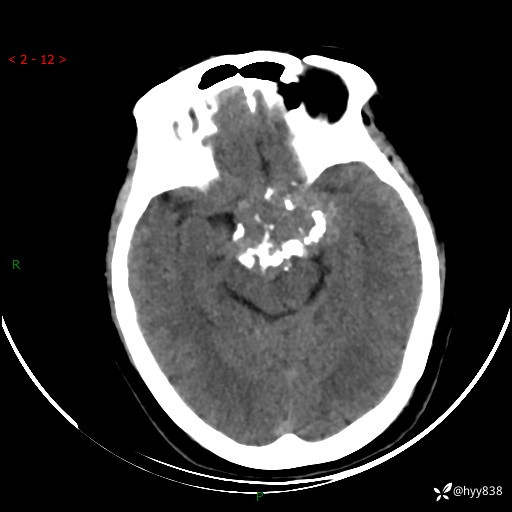

颅脑CT平扫

老年女性,视力下降3年。鞍区钙化性肿块,鉴别诊断有哪些---(有结果)

简要病史:患者3年前无明显诱因左眼出现视力下降,出现视物模糊,无头痛,无头晕,无恶心、呕吐,无意识障碍,无肢体麻木及抽搐,无心慌、胸闷,无腹痛、腹胀等不适,无旋地转感。个月前右眼视力下降,患者视物模糊逐渐下降,自诉看东西有雾感。在当地医院眼科就诊,症状无好转,行头部MR提示:鞍区肿物。现患者为求诊治来我科就诊,在当地市中医医院行头部CT:提示鞍区占位。患者现求进一步诊治来我院就诊,门诊以“鞍区肿物”收入我科。 患病以来,患者精神、饮食、睡眠尚欠佳,大小便如常,体力体重无明显变化。

临床诊断:鞍区肿物